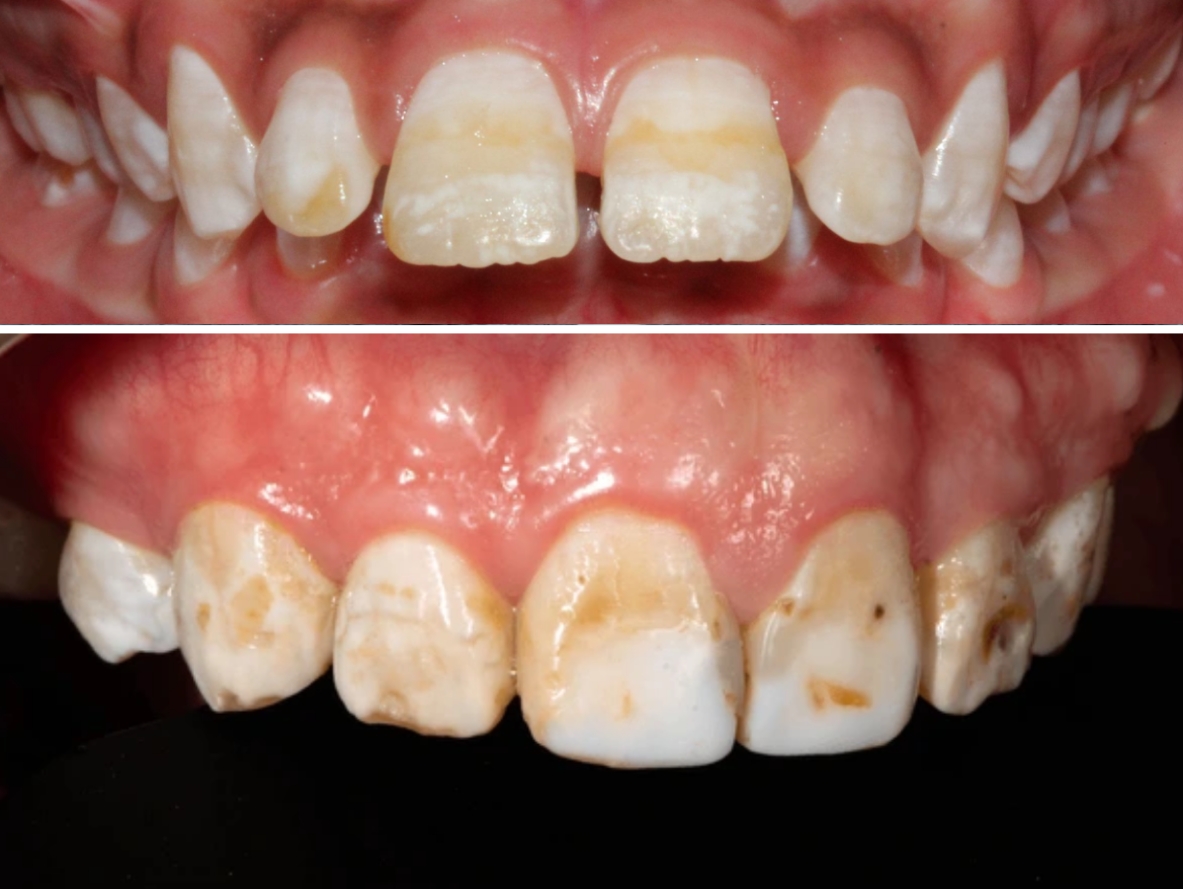

Mild cases: white spots or streaks on teeth.

Moderate to severe: brown stains, pitting, rough or chalky enamel.

Usually appears on permanent teeth, especially the front teeth.

轻度: 牙齿表面出现白色斑点或条纹。

中度至重度: 牙齿出现棕色斑点、表面粗糙或粉状、甚至有小凹坑。

多出现在恒牙,尤其是前牙。